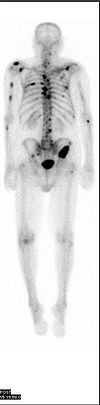

The basis of the Nuclear Medicine Bone Scan is that they put a fast decaying isotope into your blood stream and then use a fancy scintillation counter to build up images of your blood flows in the tissues they look at – in this case hips, knees and pelvic area.

The actual scanning is done in blocks of about 5 minutes, which is the length of time it takes to build up a picture of the blood flows in the tissues. Lying still is part of the drill – they have a nifty device like a big sock to hold your arms still – and a leather strap holds the feet together.